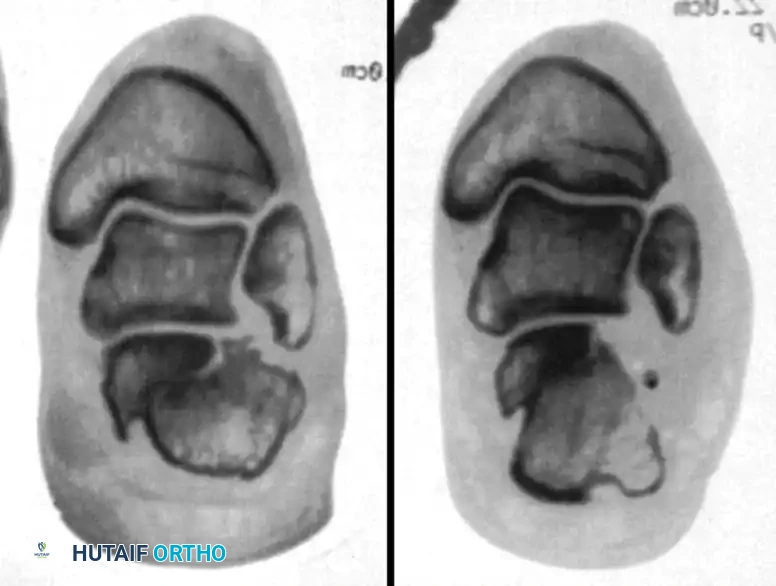

Meticulous preoperative planning is essential for successful percutaneous fixation. Standard radiographs, including lateral, axial (Harris), and anteroposterior views of the foot, should be obtained. A fine-cut computed tomography (CT) scan with sagittal and coronal reconstructions is mandatory to delineate the fracture pattern, assess the degree of posterior facet comminution, and classify the injury according to the Sanders classification system. Percutaneous techniques are most amenable to Sanders Type IIA and IIB fractures, where the posterior facet is split into two primary articular fragments.

Stephens and Saunders developed a prognostic CT-based classification system for calcaneal malunions to guide surgical reconstruction:

- Type I: Lateral wall exostosis without subtalar arthrosis.

- Type II: Lateral wall exostosis with significant subtalar arthrosis.

- Type III: Lateral wall exostosis, subtalar arthrosis, and varus malunion of the calcaneal body.